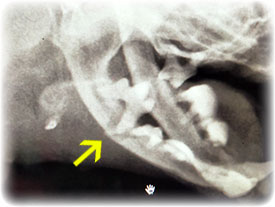

レントゲン撮ったら

まさかの下顎骨骨折という大変な事態(泣)。

特にどこか強くぶつけた感じはなかったけど

昔からの歯槽膿漏で骨が溶かされ

薄皮1枚状態で

いつこうなってもおかしくなかったらしい。